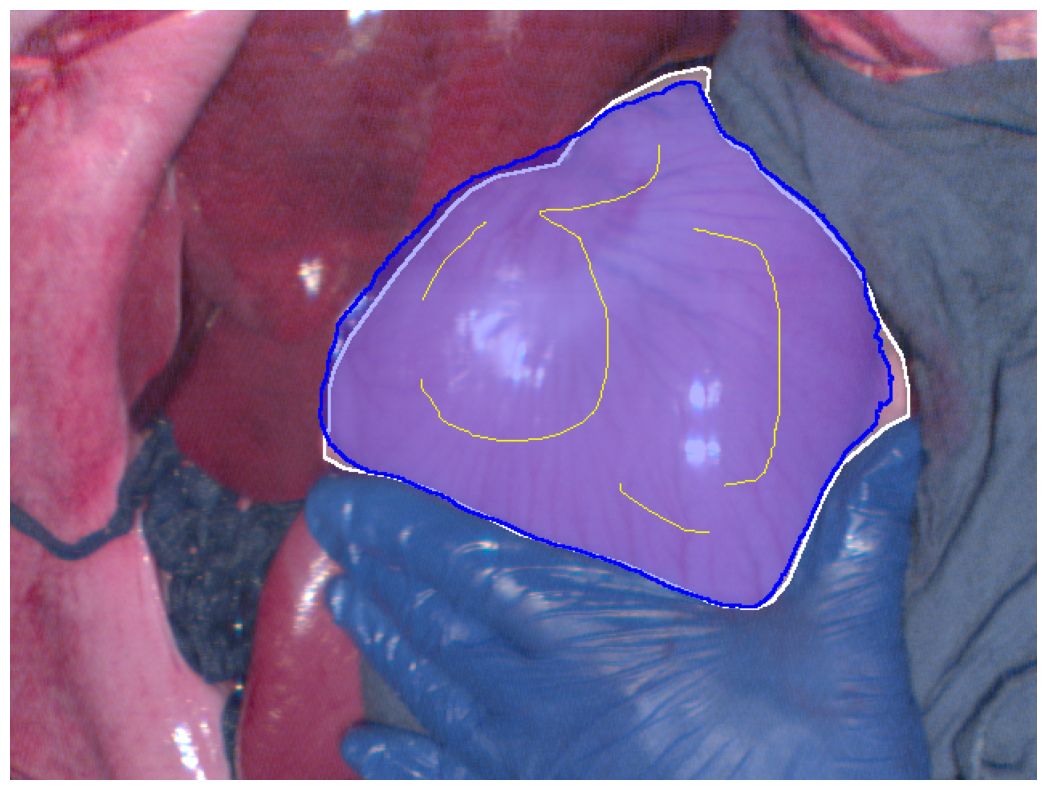

Refer to caption

(c) Reconstructed RGB best Dice segmentation result

Figure 2: Segmentation results (blue regions) at the best Dice coefficient for different methods and ground truth (white regions), along with the curves of Dice coefficient variation with threshold adjustments.

In Fig. 2, the segmentation results at the best Dice for the four different methods are displayed, along with the variation in Dice coefficients with threshold adjustments. From Fig. 2e, it can be seen that the Euclidean distance method has the lowest maximum Dice score of 0.914. The methods using geodesic distance maps generated from hyperspectral images and reconstructed RGB images achieve similar maximum Dice values, both higher than the Euclidean method. The deep learning-based feature geodesic distance map method achieves the highest maximum dice coefficient.

For the 575 images in P086, automated scribbles were generated by skeletonizing the annotation results, and segmentation results were produced using pre-mentioned four different methods. Among these, the deep learning-based feature geodesic distance map method achieved the highest average max Dice score of 0.842, demonstrating its superior performance.